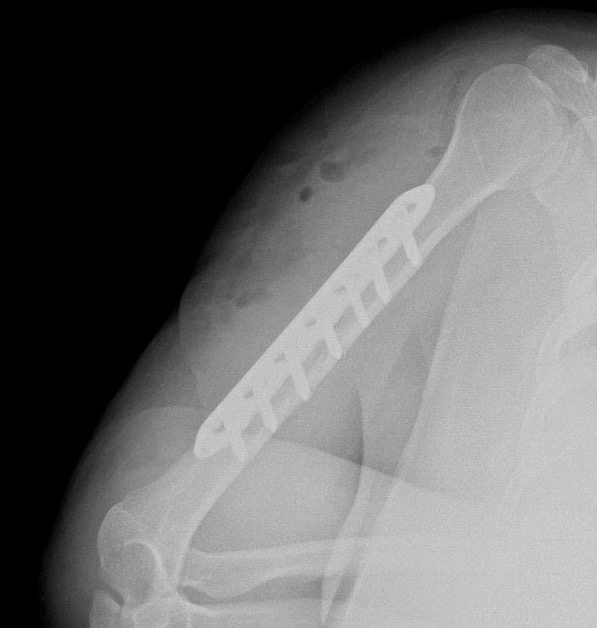

• Plaklar ve Vidalar: Kemiğin dış yüzeyine yerleştirilen metal plakalar, vidalarla kemiğe sabitlenerek kırık parçalarını bir arada tutar. Özellikle uzun kemik kırıklarında ve eklem çevresi kırıklarda kullanılır.